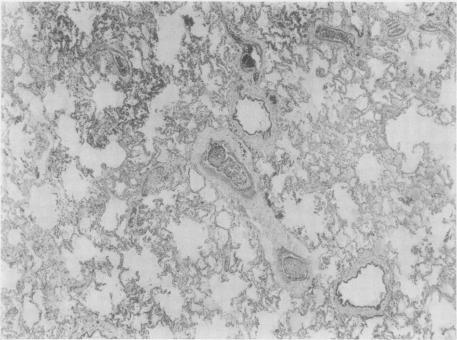

Two cases of primary breast carcinoma are described, both terminating in acute cardiorespiratory failure due to multiple tumour micro-embolism. In both cases the source of the emboli was extensive metastatic intrasinusoidal carcinomatous infliltration of the liver. The association of these two uncommon conditions has not previously been reported. A brief review of the literature pertaining to diffuse intrasinusoidal metastatic carcinomaof the liver and to carcinomatous pulmonary embolism is included. The latter condition may be commoner and of greater clinical significance than his hitherto been appreciated. Some of the factors which may be responsible for this peculiar type of tumour dissemination are discussed.

本文描述了两例原发性乳腺癌病例,两例均因多发性肿瘤微栓塞导致急性心肺功能衰竭死亡。两例中栓子的来源均为肝脏广泛的窦内转移性癌浸润。这两种罕见情况的关联此前尚未见报道。本文还简要回顾了与肝脏弥漫性窦内转移性癌和癌性肺栓塞相关的文献。后一种情况可能比以往认为的更为常见,且具有更大的临床意义。本文讨论了可能导致这种特殊类型肿瘤播散的一些因素。